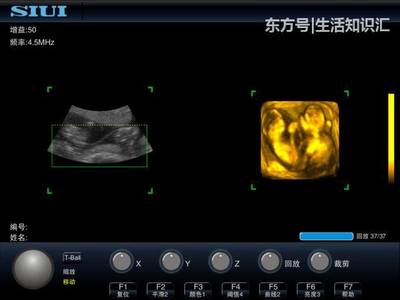

问医生。妊娠在四维彩超中起什么作用?随着科技的发展,孕期四维彩超已经成为一个大家比较熟悉的检查项目,也是孕期的常规检查项目之一。但是,四维彩超检查有什么优势呢?同时,孕妈妈为什么要做四维彩超检查?孕期四维超声可以判断胎儿的所有外观结构。四维超声最大的作用就是看胎儿的外观结构是否健全。它就像一双x光眼,能看到肚子里的宝宝。

建议孕20周后做胎儿四维彩超。2.胎儿的四肢和主要器官在怀孕20周后已经全部发育完成。最佳检查时间为孕24周、28周,因为这个阶段胎儿结构已经形成,胎儿大小和羊水适中,胎儿骨骼回声相对较小,图像清晰。所以这个时期是胎儿畸形检测最理想的时期,通过检查可以排除大部分畸形。四位彩色多普勒超声使用的仪器称为“四维彩色超声诊断仪”。

一般来说,妊娠2428周是四维彩超的最佳时间,因为胎儿24周左右是大脑快速发育的时期,这期间胎儿结构已经形成,胎儿大小和羊水适中,在子宫内的活动空间较大,胎儿骨回声的影响相对较小,图像相对清晰。四维超声在三维超声的基础上具有实时动态效果。准爸爸和准妈妈可以通过屏幕见证宝宝在妈妈肚子里的运动、呼吸、吞咽、打哈欠、吐舌头等生理活动,非常直观。

四维彩色多普勒超声是目前世界上最先进的超声诊断技术,可以从多个方向和角度观察宫内胎儿的生长发育情况,达到最佳的检测效果,为临床诊断提供准确的科学依据。一般来说,彩色多普勒超声的异常分为两个阶段。第一阶段为ⅱ类异常,在孕1822周时进行。四维是畸胎学的第二阶段,筛查的最佳时间是孕2228周,因为这一时期胎儿的四肢和主要器官已经全部发育,羊水更适合胎儿畸形筛查。